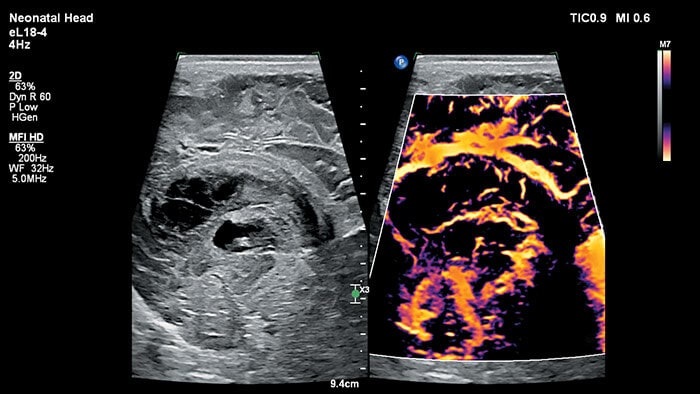

MicroFlow Imaging(MFI)は、高いフレームレートと2D画質を維持しながら、アーチファクトを低減する技術です。この技術によって、MFI HDの感度と分解能は標準的なMFI**の2倍を上回り、多くの小児臨床アプリケーションにおける血流の詳細な観察に最適です。

*EPIQ Elite超音波診断システムにおけるmC12-3トランスジューサとC8-5トランスジューサについてキャリブレーション済みの組織ファントムの内部測定比較。 **臨床ターゲットと標準測定方法を使用した、標準的なMFIとEFI HDDの内部測定比較。